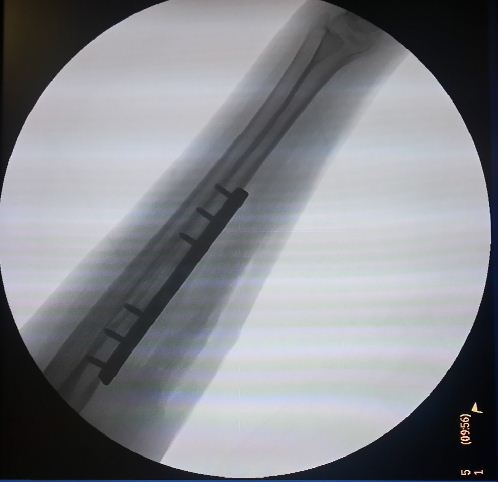

Η ελάχιστα επεμβατική οστεοσύνθεση (Minimal Invasive Plate Osteosynthesis) αποτελεί εξέλιξη της εσωτερικής οστεοσύνθεσης και περιλαμβάνει τη συγκράτηση ενός κατάγματος σε ανάταξη με τη χρήση ειδικών εμφυτευμάτων. Ο σχεδιασμός των εμφυτευμάτων αυτών δίνει τη δυνατότητα στο χειρουργό να τα τοποθετήσει μέσω μικρών δερματιών τομών χωρίς να ανοίξει την καταγματική εστία.